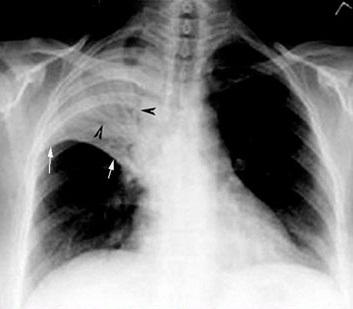

Tổn thương phổi trên phim Xquang.

Các biểu hiện của viêm phổi ở người nghiện rượu về cơ bản cũng giống như viêm phổi ở người bình thường như sốt, ho (có đờm hoặc không), có cơn rét run, đau ngực, khó thở, đau đầu, nôn, tiêu chảy, mệt mỏi, đau cơ, ý thức chậm. Khám lâm sàng có thể thấy nhịp thở nhanh, mạch nhanh. Khám phổi thấy rì rào phế nang giảm, tiếng cọ màng phổi, tiếng ran rít, ẩm, nổ, ngáy. Chụp Xquang lồng ngực thấy có tổn thương thành đám, ổ hoặc tổn thương cả thùy phổi. Tuy vậy, trong rất nhiều trường hợp, các triệu chứng của viêm phổi ở người nghiện rượu thường rất kín đáo do bệnh nhân thường xuyên say xỉn và hoạt động của hệ miễn dịch kém nên các biểu hiện như đau ngực, sốt... không xuất hiện rầm rộ. Người bệnh thường được nhập viện trong hai tình huống: một là suy hô hấp nặng, hai là tình trạng sốc (sốc giảm thể tích do mất dịch hoặc sốc nhiễm khuẩn). Bệnh nhân khó thở dữ dội, tím môi đầu chi, mạch nhanh nhỏ, da tái lạnh, huyết áp tụt. Chụp Xquang lồng ngực thấy phổi trắng xóa một phần hoặc toàn bộ. Những trường hợp này thường tiến triển xấu nhanh và tử vong cho dù có được hồi sức tích cực.